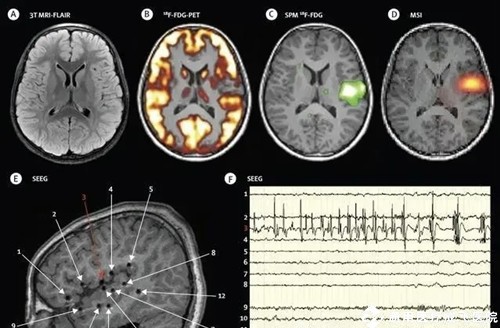

影像学检查

头颅CT和MRI(磁共振)检查,属于癫痫的病因检查,用以了解脑部结构有无异常,如有无巨脑回、皮层发育不良、脑血管畸形、脑肿瘤、结节性硬化、颅内出血、钙化等。